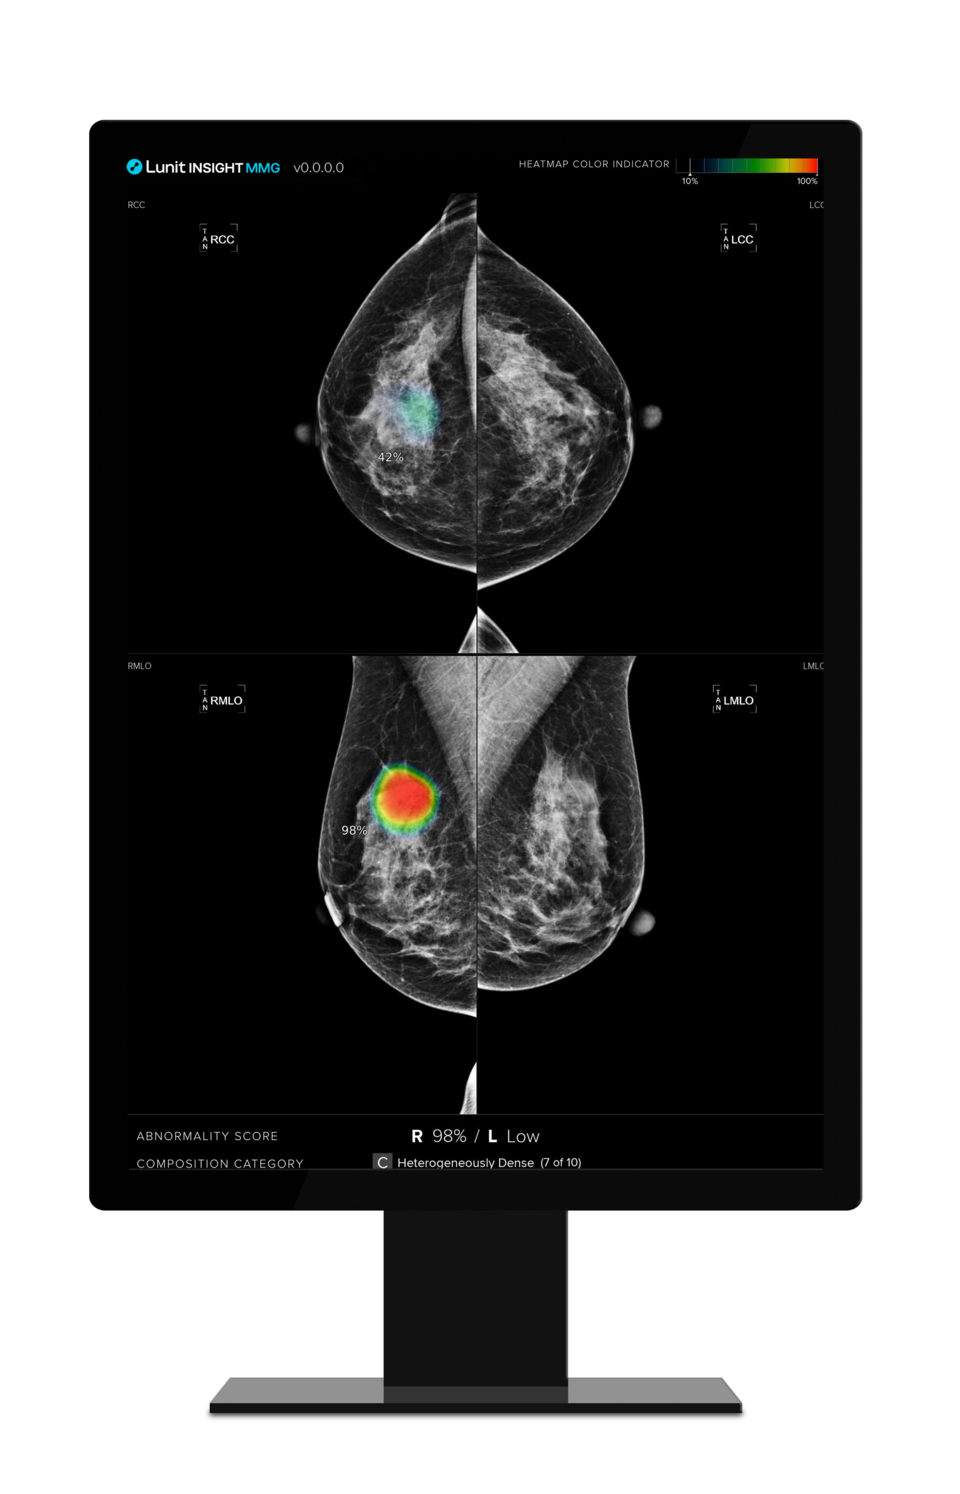

또 지금까지 대부분의 연구는 유방암 진단을 이미 받은 환자의 데이터를 분석하는 후향적 연구였지만, 이번 연구에서는 '루닛 인사이트 MMG'를 의료현장에 적용하고 실시간 환자 분석을 통해 전향적으로 AI의 실제 임상적 효과를 확인할 예정이다.

연구진은 리즈 대학병원 유방 클리닉에 방문하는 환자 5500명을 대상으로 오는 2025년말까지 연구를 마친다는 계획이다. 이 중 절반인 2750명은 유럽의 유방암 판독 규정인 이중 판독(Double Reading)으로 전문의 두 명에 의한 판독을 받게 된다. 나머지 절반은 전문의 두 명이 루닛 AI 솔루션을 활용해 판독하는 방식으로 진행해 결과를 비교 분석할 예정이다.